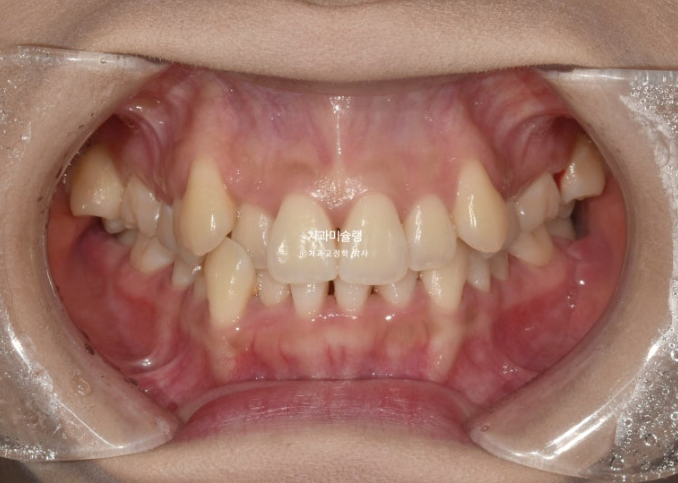

2년 전 덧니 교정치료를 위해 내원한 환자분입니다.

중심선 문제, 블랙트라이앵글, 과개교합, 반대교합, 가위교합 등이 보입니다.

발견되는 부정교합의 종류들을 나열해보자면

중심선 불일치

과개교합

대구치 가위교합

심한 덧니

전치부 반대교합

부정교합은 아니지만 블랙트라이앵글

정도가 되겠습니다.

이 정도라면 작은어금니 4개 발치교정 진단을 할만도 하지만

입술 돌출이 없고 입술이 얇아 발치교정이 고민되는 상황입니다.

결국 환자분과 논의 후 입매 변화 없는 비발치로 진행하기로 합니다.